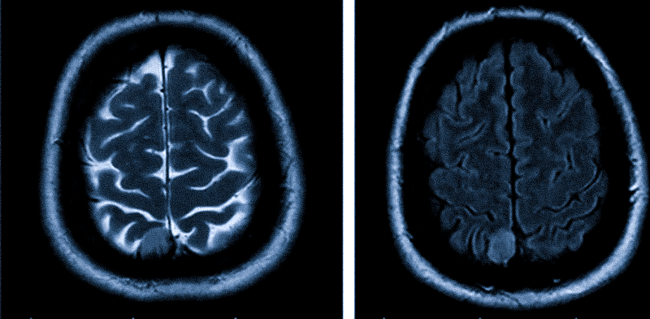

МРТ диагностика опухолей головного мозга является решающим этапом в данном исследовании. Она дает возможность сделать снимки под разными углами, которые помогают специалистам-онкологам составить изображение опухоли в 3D. Снимки, полученные при помощи МРТ, позволяют получить очень четкое изображение новообразований, расположенных рядом с костями, а также небольших и находящихся на ранних стадиях развития опухолей, в том числе и опухолей ствола головного мозга.

МРТ дает максимально детальное изображение сложных структур мозга. Благодаря этому можно получить снимок головного мозга в 3D, что позволяет специалистам точно определить местонахождение новообразования или аневризмы.

Наиболее информативны в диагностике опухолей центральной нервной системы магнитно-резонансная томография (МРТ) и компьютерная томография (КТ). Эти исследования часто проводятся с контрастированием.

Обычно диагностика опухоли головного мозга начинается с магнитно-резонансной томографии (МРТ).Как только МРТ показывает, что в головном мозге есть опухоль, наиболее распространенный способ определить тип опухоли головного мозга — это посмотреть на результаты образца ткани после биопсии или операции. Эти тесты и процедуры описаны ниже более подробно.

Магнитно-резонансная томография (МРТ). МРТ использует магнитные поля, а не рентгеновские лучи, для получения подробных изображений тела. МРТ можно использовать для измерения размера опухоли. Перед сканированием наносится специальный краситель, называемый контрастным веществом, для создания более четкого изображения.Этот краситель можно вводить пациенту в вену или давать в виде таблетки или жидкости для проглатывания. МРТ создают более подробные изображения, чем КТ (см. Ниже), и являются предпочтительным способом диагностики опухоли головного мозга. МРТ может касаться головного, спинного мозга или того и другого, в зависимости от типа подозреваемой опухоли и вероятности ее распространения в ЦНС. Есть разные виды МРТ. Результаты нейроанализа, проведенного терапевтом или неврологом, помогают определить, какой тип МРТ использовать.